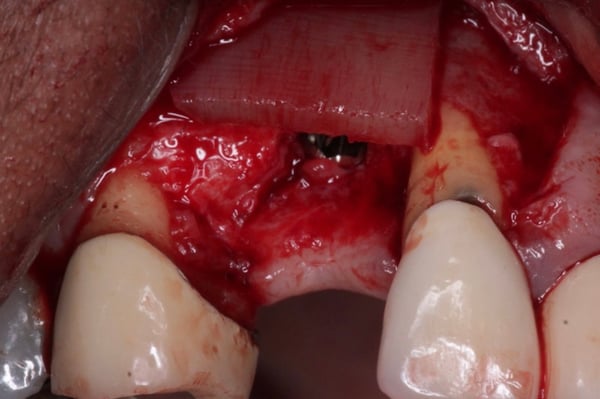

Tension - Relief for Primary Closure

When performing extensive GBR we want to insure the primary closure of the flap margins over the graft and membrane.